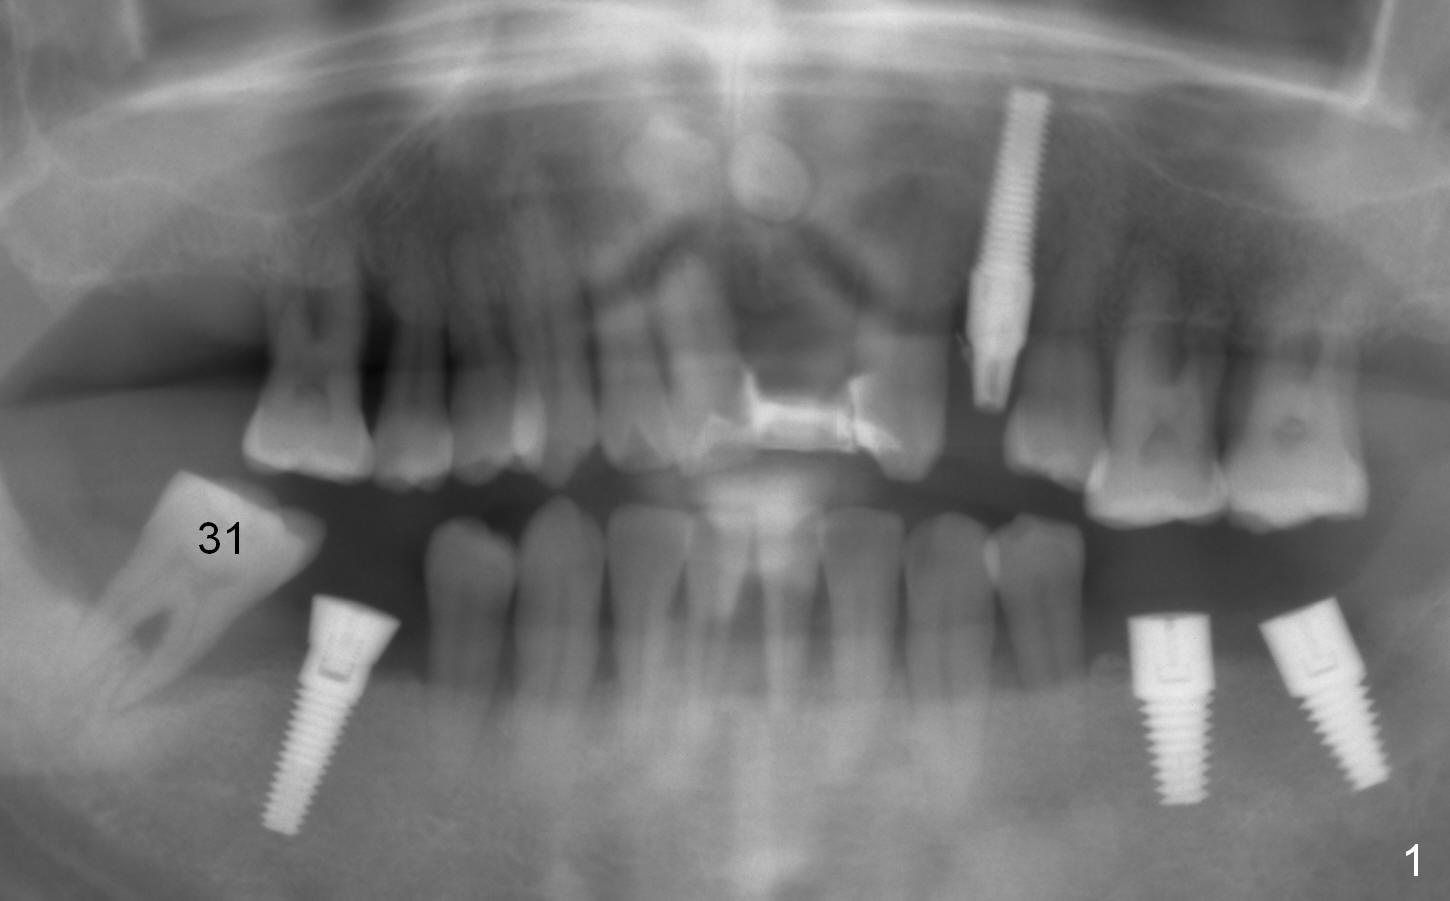

A 44-year-old man is a typical patient with chronic periodontitis (Fig.1).  Periimplantitis develops following immediate implant at #31 (Fig.2).  The symptom (bleeding) improves after bone graft and use of Water Pik.  Now the tooth #14 appears to be non-salvageable because of gingival hemorrhage and deep pockets after previous osseous surgery.  To prevent periimplantitis, an immediate implant does not need to be large or long.  It has to be placed deep, and in the middle of the native bone, surrounded by bone graft.  To facilitate wound healing, draw 3 tubes of blood for PRF.  One of them is processed for plug in case of sinus lift.  To prevent the buccal gingiva collapse, the buccal portion of the immediate provisional should extend into the socket.  If the gingiva is around 4 mm, use IBS implant (Fig.3,4).  Otherwise, a SM implant will be used after extraction (Clindamycin), since abutments have cuffs as long as 4.5 and 6 mm so that it is easy to place an implant as deep as possible.  Initial depth will be 9 mm (bone-level), followed by Magic Drill (5.3 mm, if possible) and Magic expanders (4.3x10 and 4.8x11 mm, bone density 26-300 units).